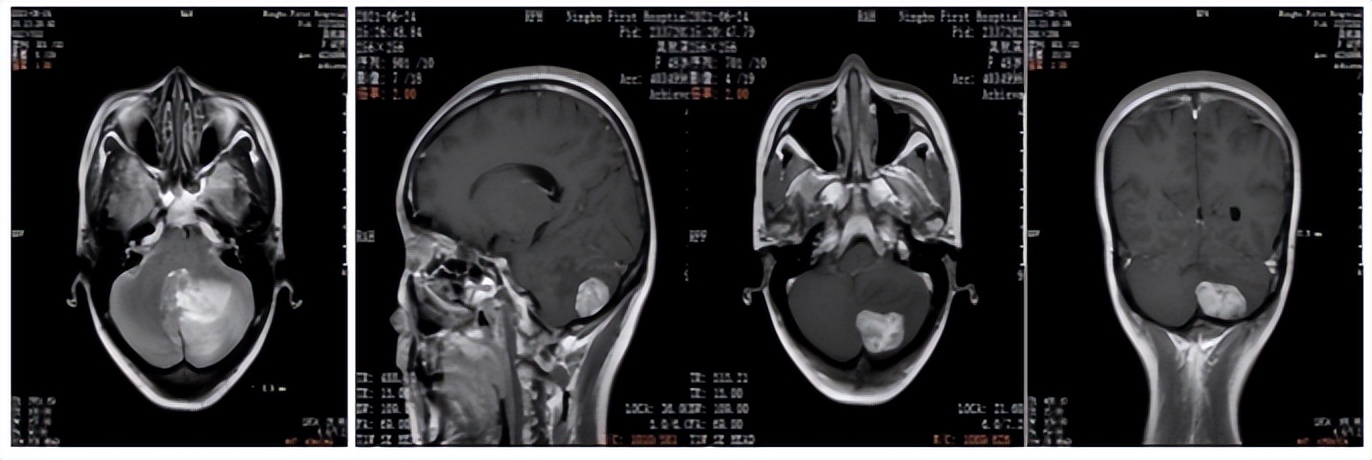

2021年6月颅脑增强MRI:左侧小脑占位,考虑转移瘤。

图2. 颅脑增强MRI

2021年6月:出现头晕头痛1周,检查颅脑增强MRI:左侧小脑占位,考虑转移瘤。

2022年5月颅脑增强MRI:左侧小脑肿瘤切除术后改变。

疗效评价CR,继续维持曲妥珠单抗(汉曲优)+吡咯替尼+卡培他滨治疗方案

图3. 颅脑增强MRI